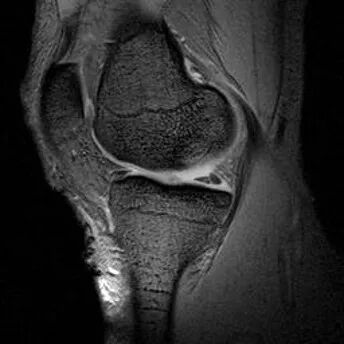

1、半月板体部的撕裂在矢状面上表现为蝶形的半月板内出现与长轴垂直的线状高信号2、前后角的放射状撕裂因与矢状面平行而表现为III级高信号3、好发于半月板的内侧1/34、外侧半月板多见

半月板放射状撕裂